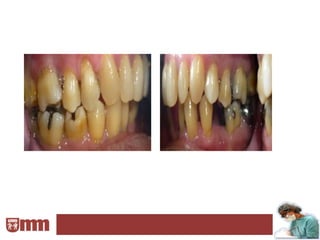

El examen bucal debe ser completo e incluir inspección

visual y palpación de piezas dentarias y tejidos,

exploración y sondaje periodontal, seriadas radiográficas,

test de vitalidad de piezas en estado crítico y un examen

de modelos montados en articulador.